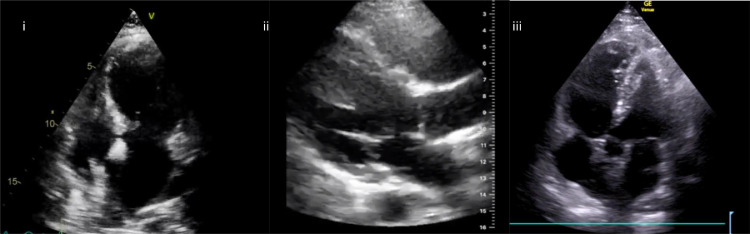

When considering echocardiographic findings in COVID-19, numerous mechanisms of cardiac injury have been described (Fig 2 ). These include myocarditis, global cardiac dysfunction, right ventricular failure, and acute myocardial infarction (AMI) (video 4). The European Society of Cardiology guidance on COVID-19 echocardiography advises only patients with cardiovascular compromise should be scanned, and these scans should be focused in nature (Table 1 ).5

Fig. 2.

Echocardiographic findings in COVID-19: (i) apical 4-chamber view—apical bowing in Takotsubo cardiomyopathy secondary to COVID-19; (ii) parasternal long-axis view—dilated right ventricle with septal bowing in a patient with COVID-19 and raised pulmonary pressures; and (iii) apical 5-chamber view—McConnell’s sign in a patient with COVID-19 and bilateral pulmonary emboli. COVID-19, coronavirus disease 2019.